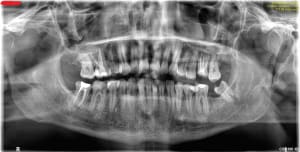

20-04-2021 Panoramique Début.JPG